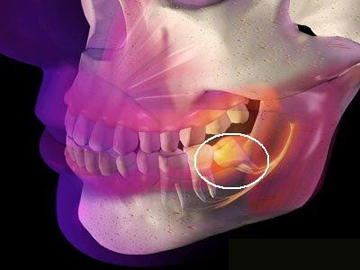

1、智齒位置:智齒的位置是影響拔除費(fèi)用的重要因素之一,智齒的位置越深,手術(shù)難度越大,拔除費(fèi)用也就越高。

2、手術(shù)復(fù)雜性:拔智齒手術(shù)的復(fù)雜性也會(huì)影響費(fèi)用,如果智齒生長(zhǎng)位置正常,手術(shù)相對(duì)簡(jiǎn)單;如果智齒被埋在骨頭里,需要切開(kāi)牙齦和骨頭,手術(shù)難度增大,費(fèi)用相應(yīng)增加。